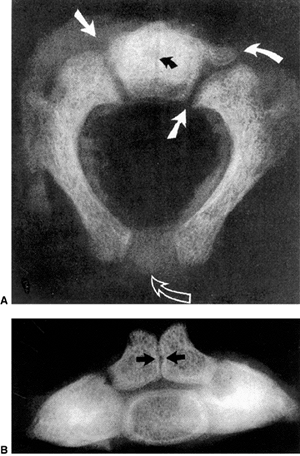

Figure 22.1 A:

Cross-sectional radiograph of C1 in a full-term neonate. The posterior ossification centers are present. No ossification is present in the anterior cartilage. The transverse ligament (arrow) separates the dens (D) from the spinal canal (S). B: Anteroposterior radiograph of C1 in a full-term neonate. (From Ogden JA. Radiology of postnatal skeletal development. XI. The first cervical vertebrae. Skeletal Radiol 1984;12:12–20.) |

![]() |

Figure 22.2 A: Cross-sectional radiograph of C2 in a neonate. The neurocentral (solid white arrows) and posterior (open arrow)

synchondroses are evident. A small area of accessory ossification is present in the right neurocentral synchondrosis anteriorly (curved arrow at top right). Also note the central linear radiolucency (black arrow) indicating the synchondrosis between the dens ossification centers. The posterior ossification centers extend into the eventual vertebral body. B: Anteroposterior radiograph of C2 in a neonate. In this specimen, the dens ossification centers have not fused, leaving a midline synchondrosis (arrows) that extends from the chondrum terminale to the dentocentral synchondrosis. The superior margin of the eventual vertebral body is above the lower level of the dens. The neurocentral synchondroses are continuous with the “ring apophyseal” cartilage inferiorly, the facet cartilage inferiorly, and the dentocentral synchondrosis superiorly. (Ogden JA. Radiology of postnatal skeletal development. XI. The first cervical vertebrae. Skeletal Radiol 1984;12:12–20.) |